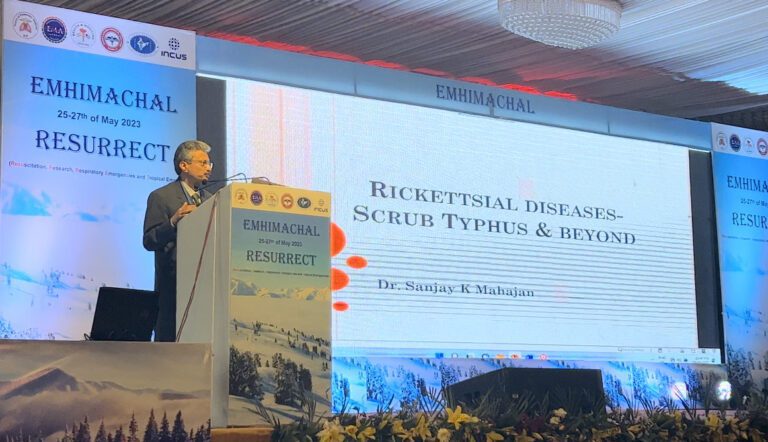

EMHIMACHAL पर आधारित रेस्पिरेट्री डीजीज इमरजेंसी को कैसे ग्रास रूट स्तर पर मशीनों के अभाव के बावजूद...

EMHIMACHAL पर आधारित रेस्पिरेट्री डीजीज इमरजेंसी को कैसे ग्रास रूट स्तर पर मशीनों के अभाव के बावजूद...